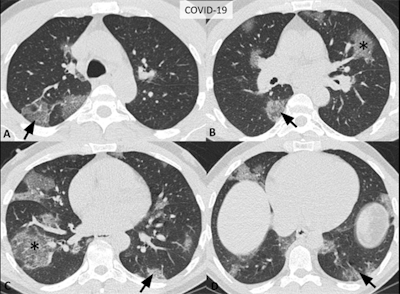

- Typical appearance: Commonly reported CT findings of greater specificity for COVID-19 pneumonia, including peripheral, bilateral ground-glass opacity, and crazy-paving pattern. Principal differential diagnoses include viral pneumonias, especially influenza, and acute lung injury patterns such as organizing pneumonia.